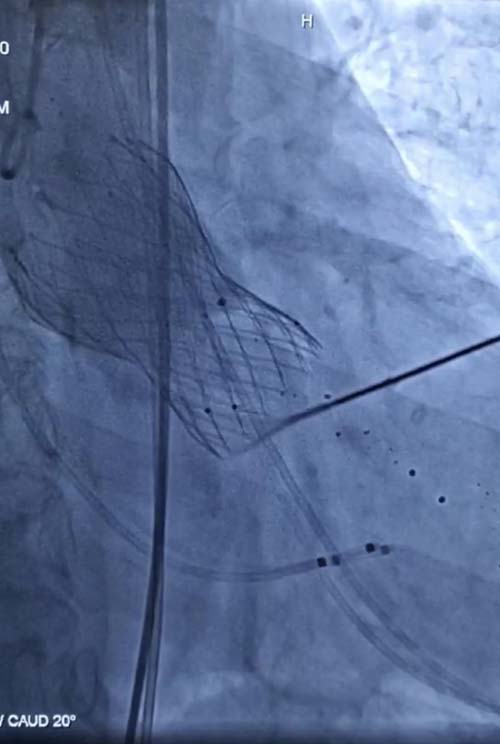

术前,王勇副主任联合心外科、麻醉手术科、超声科及介入诊疗科全面评估,制定了完善的手术方案。术中,王勇和李少华、赵鹏医生在广东省人民医院李捷教授的指导下,在局部麻醉下应用极简式方案顺利植入一枚人工主动脉瓣瓣膜,术后经胸心脏彩超提示瓣膜位置良好,主动脉瓣无明显反流。